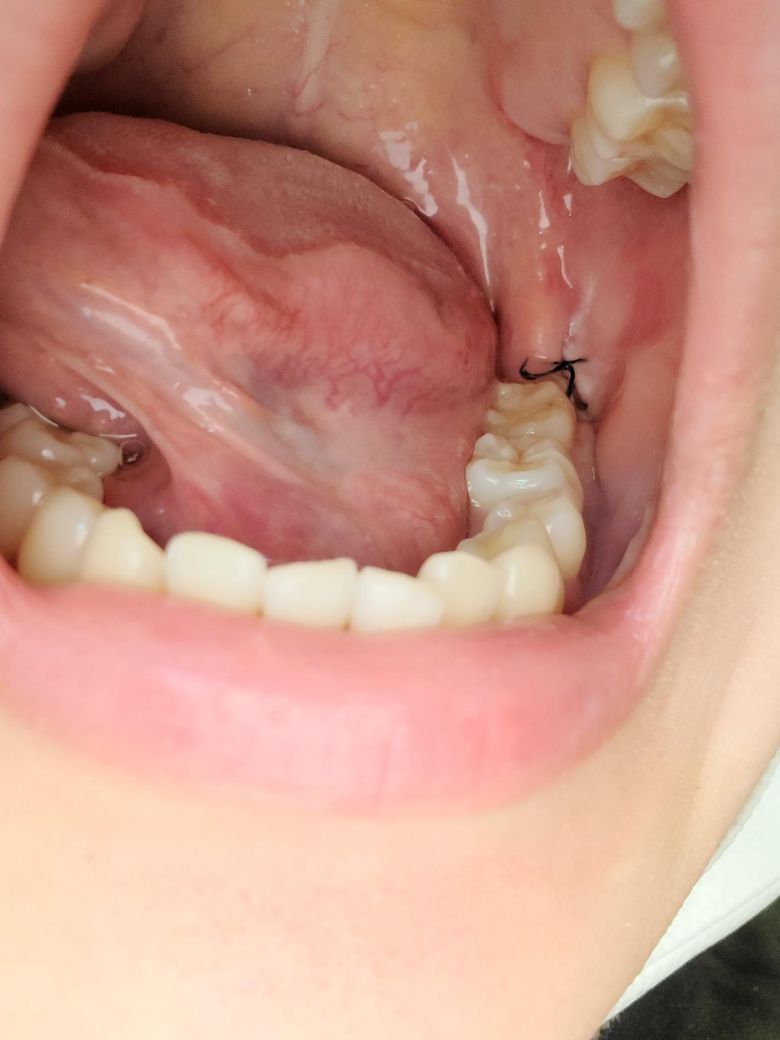

매복사랑니 화요일에 빼고 지금 3일정도됬는데 사진으로 보다시피 하얀색뭐가있어서요 이게 드라이소켓?이라는건지 아니면 그면 음식물이 낀건지 어제도 있길래 이쑤시개 로 뺐더니 없어지긴하더라고요? 건드리면 안됬던건지 궁금해요!

드라이소켓은 발치부위 상처에서 피가 딱지로 굳지 못하여 발생하고 약으로 조절할수 없는 통증이 동반됩니다. 발치 부위에 낀 음식물은 제거해주면 됩니다. 건강하세요.

딱히 드라이소켓의 양상은 아닌 것으로 보입니다. 아마도 이물질이었을겁니다. 이쑤시개는 자극이 되니 그거보다는 물가글해서 음식물찌꺼기 제거해주세요